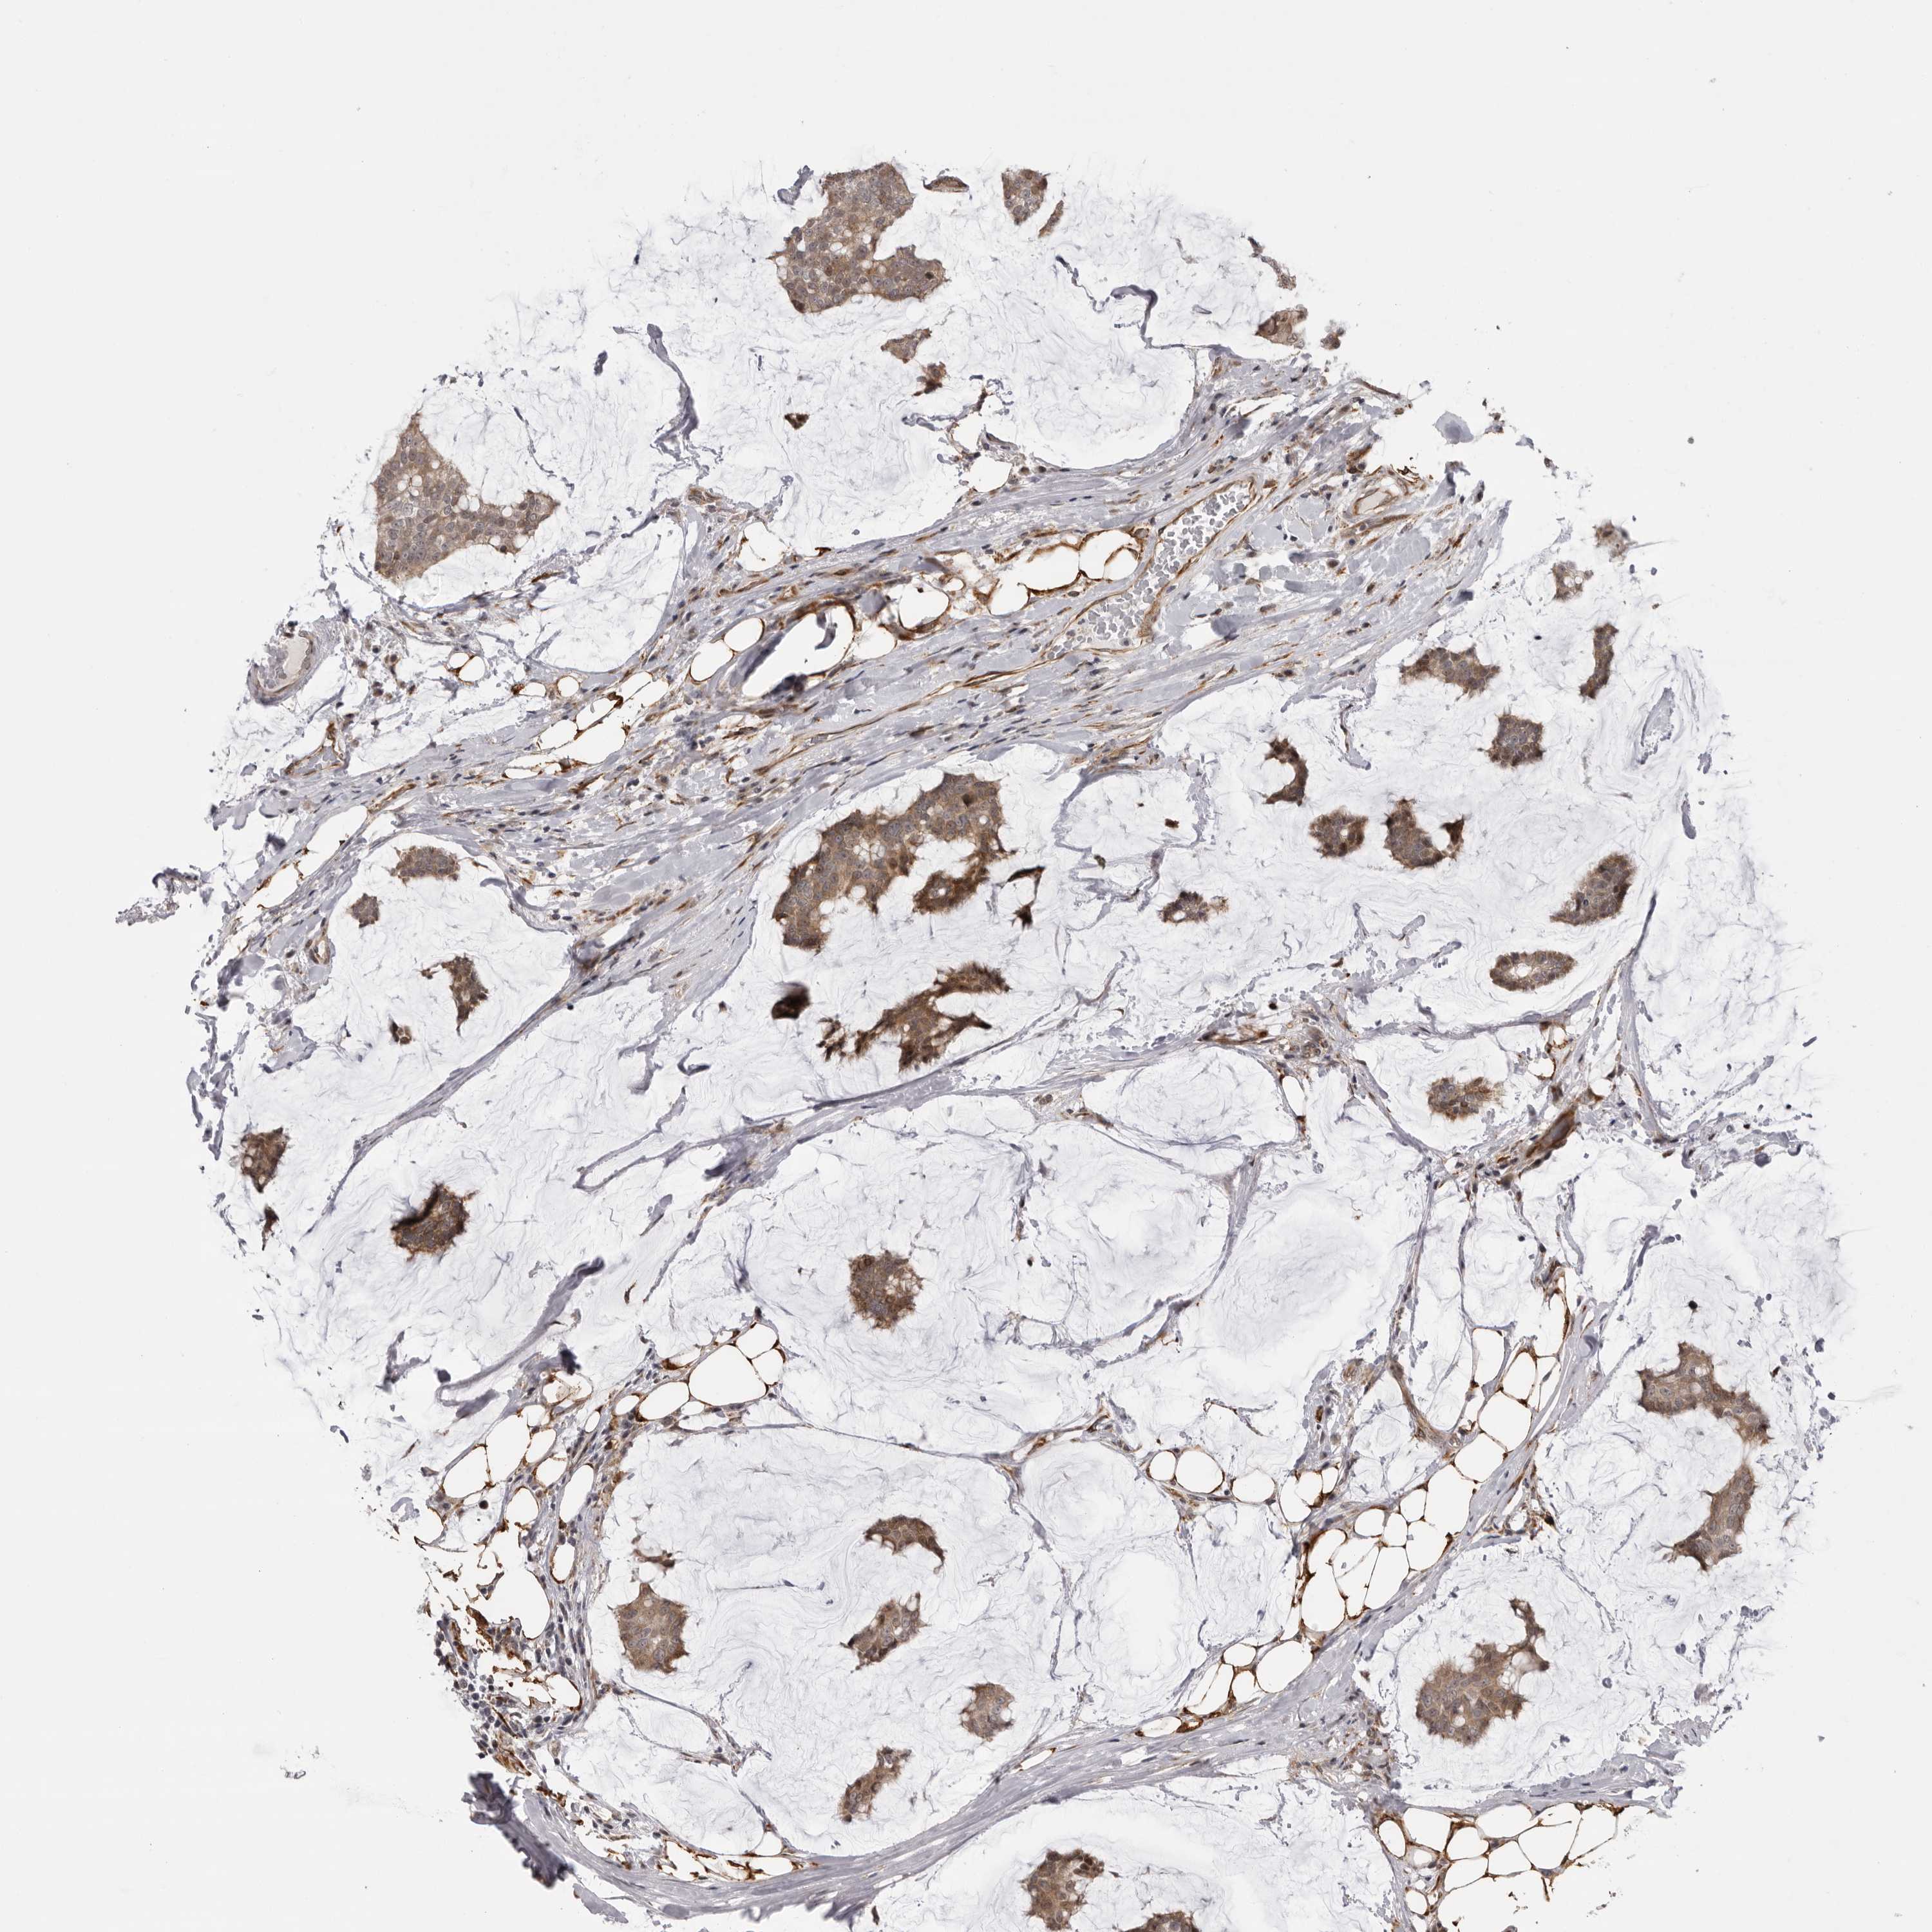

BRCA TCGA BRCA VALIDATION PROTEIN EXPRESSION

ANTIBODIES

AND

VALIDATION